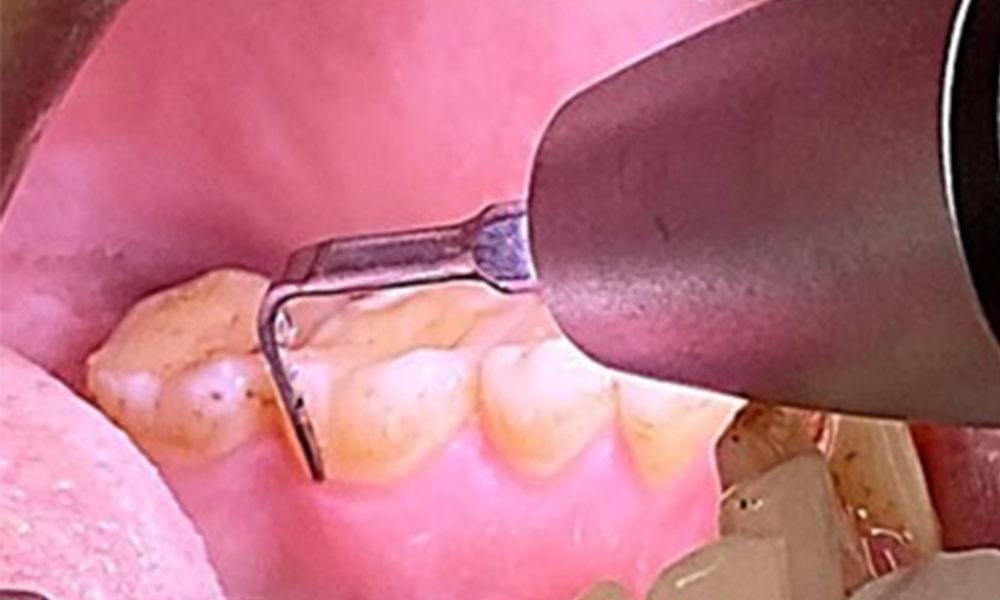

Ziel ist es durch supra- und subgingivale Biofilmentfernung das Erkrankungsrisiko zu kontrollieren. Die Wahl der Instrumente erfolgt

bedarfsgerecht. Zunächst sind Zahnstein und ggf. Konkremente mit Ultraschall und / oder Handinstrumenten zu entfernen (Abb. 10).

Anwendung eines piezobetriebenen Ultraschallgerätes in Rg 36

Abb. 10 Anwendung eines piezobetriebenen Ultraschallgerätes in Rg 36 lingual (hier Proxeo Ultra, Firma W&H), © Dr. R. Krapf